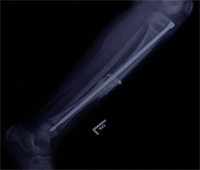

Also known as congenital "Anterolateral Bowing of Tibia" or CPT is a rare condition seen in infants and children. The tibia is bowed and the apex of the deformity in anterior and lateral in the sagittal and coronal plane respectively. Incidence is 1: 140,000. This type of bowing is pathognomomic of CPT or Congenital Pseudarthrosis of tibia, leading to a recalcitrant non-union of the tiba and fibula. Almost 50% of cases are associated with Neurofibromatosis type I or fibrous dysplasia. The deformity may be present at birth or occurs as a painless stress fracture when child starts to walk. The typical site of deformity is in the lower third of the leg and both tibia and fibula may be involved. Radiographs reveal typical bowing and the tibia may have sclerotic edges, cortical tapering, cyst formation and sometimes obliteration of meduallary cavity. CPT that Require Treatment

Rush Rodding Periosteal Grafting

Newer Fassier - Duval rod in an older child. About CPTCPT is a disorder of the tibia where there is a propensity for recurrent fractures, poor healing of bone and need for multiple operations. Current methods of treatment of CPT have evolved to give much more consistent results than previously possible. Special methods are available to achieve union. |